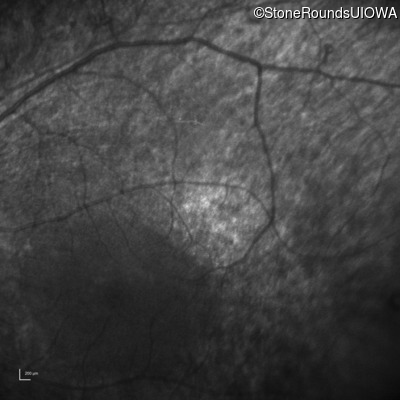

Infrared Fundus Photograph - Left - No Light Perception

Exemplar